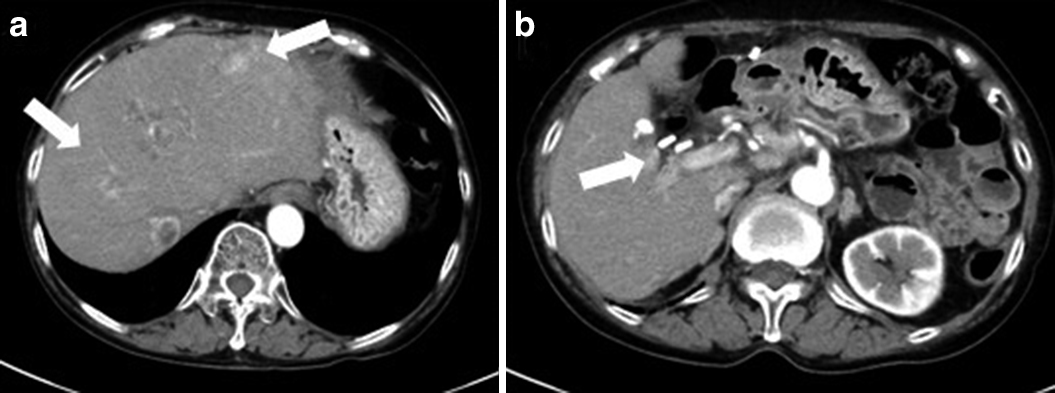

腹部造影CT所見:上腹部を中心に多量の血性腹水を認めた.肝門部~左葉外側区域にかけて顕著な造影剤の血管外漏出像を認め,肝右葉S6内側の6.2 cm大の転移巣は3.7 cm大に縮小し,内部の造影効果がなく壊死を示唆する所見を呈していた(Fig. 4).

Abdominal dynamic CT showed abundant bloody ascites in the upper abdomen and extravasation ranging from the hepatoduodenal ligament to beneath the lateral segment of the liver (arrows) (a, b). The metastatic liver tumor in S6 segment became necrotic and shrunk (arrowheads) (c, d).

2017年8月,ソマトスタチン受容体シンチグラフィで多発肝転移と膵周囲や胃小彎リンパ節に集積を認めたことと,膵切除標本の免疫染色検査でSSTR2Aが陽性であったことより,ランレオチド120 mg/月の投与を開始した.2018年1月の腹部造影CTにて早期濃染する多発肝転移巣の増大を認めたため(Fig. 6),3月からストレプトゾシン1,000 mg/m2の1週間間隔投与を開始した.2018年7月の腹部造影CTにて多発肝転移巣は著明に縮小し,RECIST効果判定PRと診断した(Fig. 7).現在,ストレプトゾシンを計55回投与継続しており,初回手術後8年7か月,肝転移破裂後1年11か月,肝転移巣は縮小を維持して生存中である.

Abdominal dynamic CT showed multiple, huge metastatic liver tumors that were markedly enhanced in the early phase 8 months after the arterial embolization (arrows) (a, b).

Abdominal dynamic CT showed that the multiple metastatic liver tumors shrunk remarkably at 4 months after the start of administration of streptozocin (arrows) (a, b).